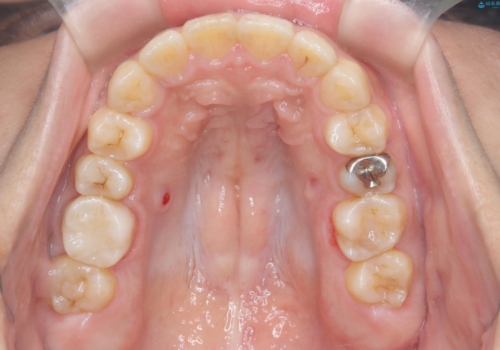

- 主訴:学生時代に矯正治療したが、後戻りしてしまった。上下前がのガタつきを治したい。

ワイヤー矯正(審美装置)非抜歯 治療期間:1年8か月

途中、大臼歯の遠心移動のためリンガルアーチを使用しています。